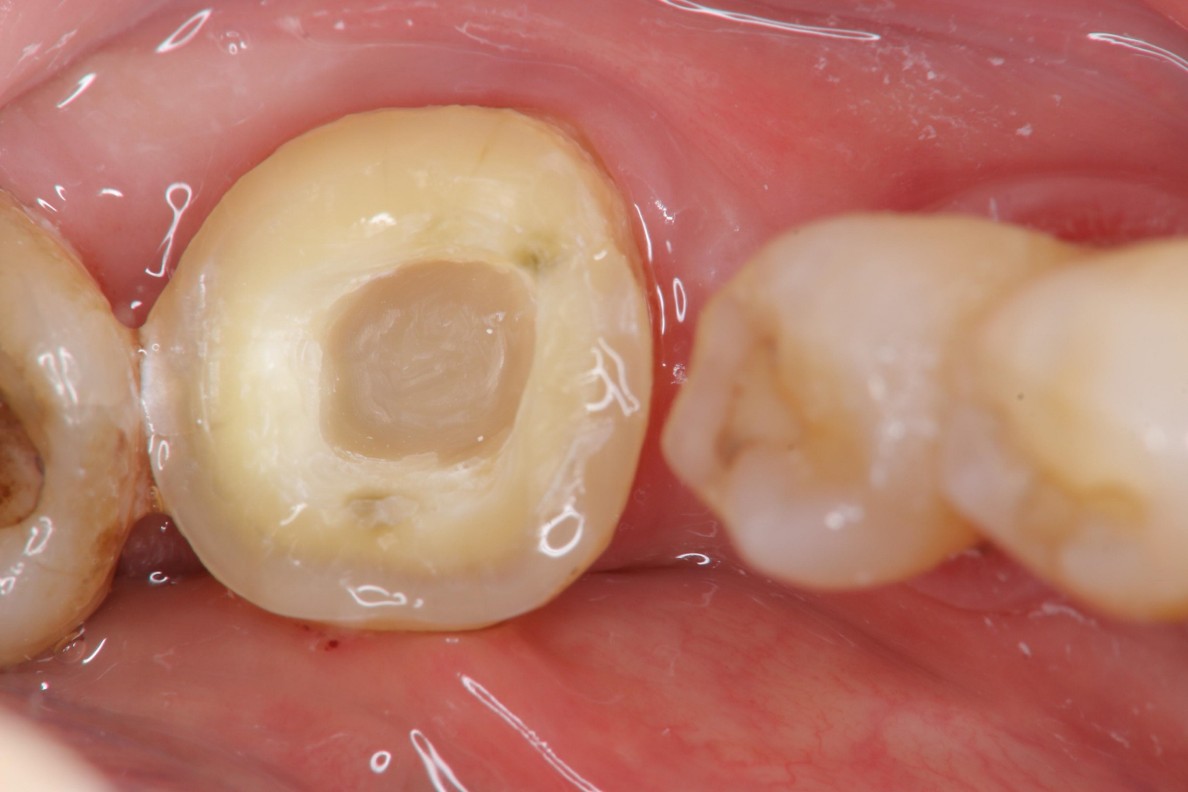

陶瓷冠塊體製備

照相比色